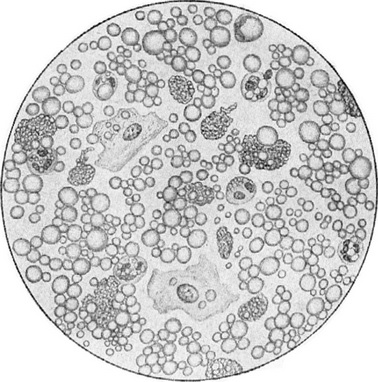

Молозиво - густа, жовтого кольору і дещо клейка рідина, високої питомої ваги (1050-1060), свертывающаяся при кип'ятінні і містить, як показує мікроскопічне дослідження, поряд з жировими кульками різної величини, ще й так звані молозивні тільця, великі, нерівної форми клітини, наповнені дрібними жировими крапельками (рис. 90). На думку більшості авторів, це - лейкоцити в стадії жирового переродження. Крім молозивных тілець і полулуний, молозиво містить лейкоцити, причому, за спостереженнями деяких авторів, переважання багатоядерних форм вказує на добру, а одноядерних форм - на погану лактационную здатність грудної залози.

Рис. 90. Жіноче молозиво під мікроскопом.